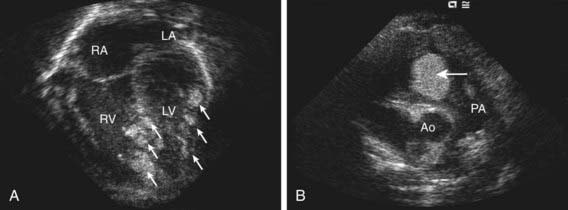

The vast majority of tumors originating from the heart are benign. Rhabdomyomas are the most common pediatric cardiac tumors and are associated with tuberous sclerosis in 70-95% of cases (Chapter 589.2). Rhabdomyomas may occur at any age, from fetal life through late adolescence. They are often multiple, can occur in any cardiac chamber, and originate within the myocardium extending, often, into the atrial or ventricular cavities (Fig. 435-1). Depending on their location and size, they can result in inflow or outflow obstruction leading to cyanosis or cardiac failure. Atrial and ventricular arrhythmias have been reported with rhabdomyomas, and on occasion, ventricular pre-excitation (Wolff-Parkinson-White) is present on ECG.

Figure 435-1 Echocardiograms demonstrating rhabdomyomas. A, Apical four-chamber view showing multiple rhabdomyomas (arrows) within the septum and left ventricular myocardium. B, Short-axis view showing a large rhabdomyoma (arrow) extending into the right ventricular outflow tract. Ao, ascending aorta; LA, left atrium; LV, left ventricle; PA, pulmonary artery; RA, right atrium; RV, right ventricle.